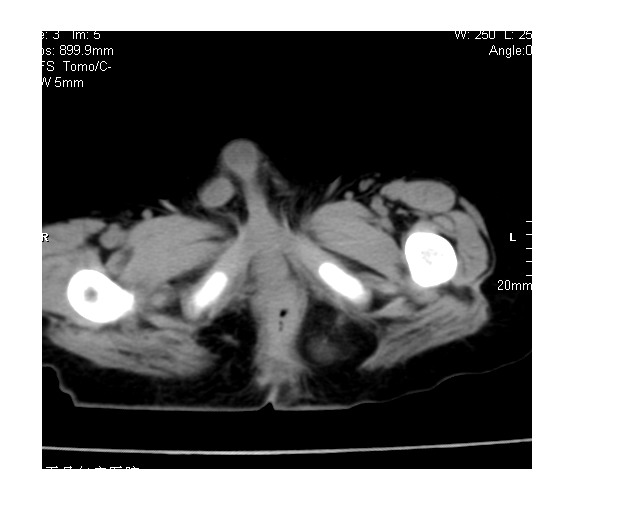

以下是引用lkc8963在2008-3-16 12:49:00的发言:[br]盆底巨大混杂密度肿块,富含多种组织成分包括脂肪/液体/软组织/钙化,边界清楚,向前压迫肠管及膀胱,向后突入骶尾部皮下脂肪层,首先考虑畸胎瘤,诊断时需要与脊柱裂/囊性淋巴管瘤等区别。